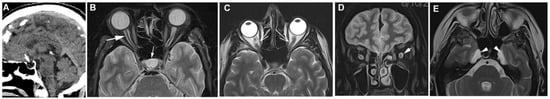

Some visible modifications derive from bony erosion from IIH, such as empty sella, meningocele, and foramen ovale widening, while others are due to mechanical deformation from IIH (posterior ocular globe flattening, vertical tortuosity of the optic nerve, transverse sinus venous stenosis), or a limitation of normal flow of fluids in the optic nerve sheath with optic nerve head protrusion and distention of the optic nerve sheath [35,36] (Figure 1).

In a meta-analysis [35] of MRI modification associated with intracranial hypertension, the empty sella had a pooled sensitivity of 62.2% and a pooled specificity of 90.7%, with absolute pituitary area <151 mm2 being the most sensitive modification (95.5%). Posterior globe flattening had a sensitivity of 56.3% and specificity of 95.3%, optic nerve head protrusion had a sensitivity of 29.1% and specificity of 97.0%, and optic nerve sheath distension had a pooled sensitivity and specificity of 68.6% and 86.1%, respectively, with individual sensitivity of 78.8% and specificity of 94.2% for a maximum optic nerve sheath diameter > 5.60 mm.